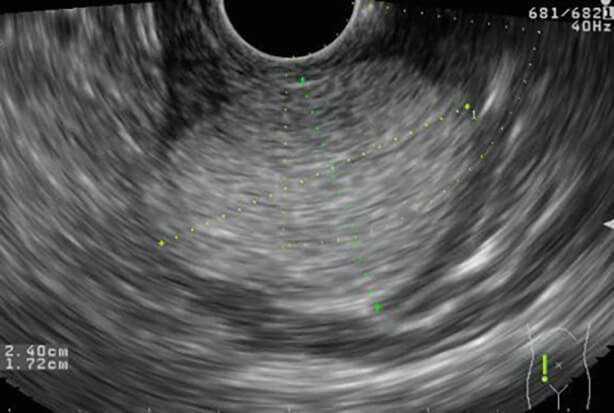

Εικόνες 1, 2: Εξελκώµενο GIST (GastroIntestinal Stromal Tumour) στοµάχου

Εικόνα 2